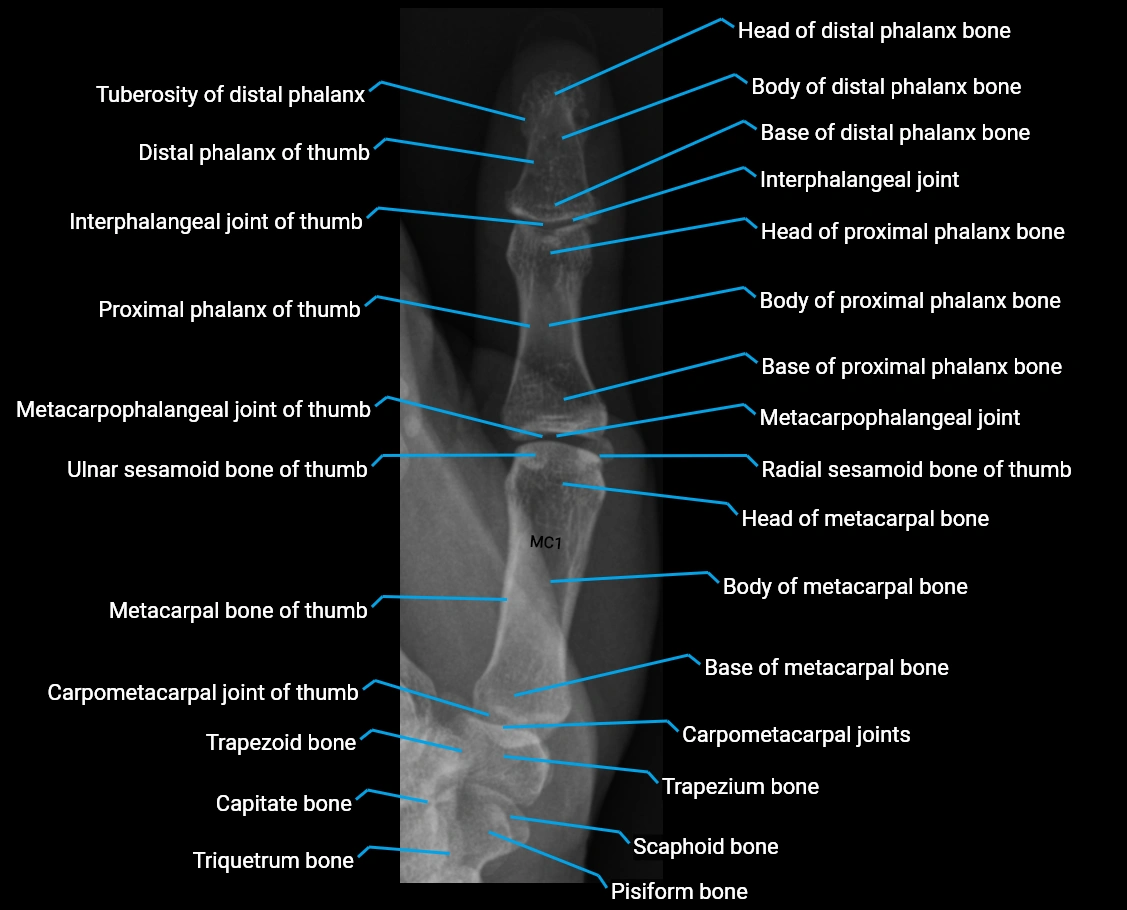

X Ray image

image